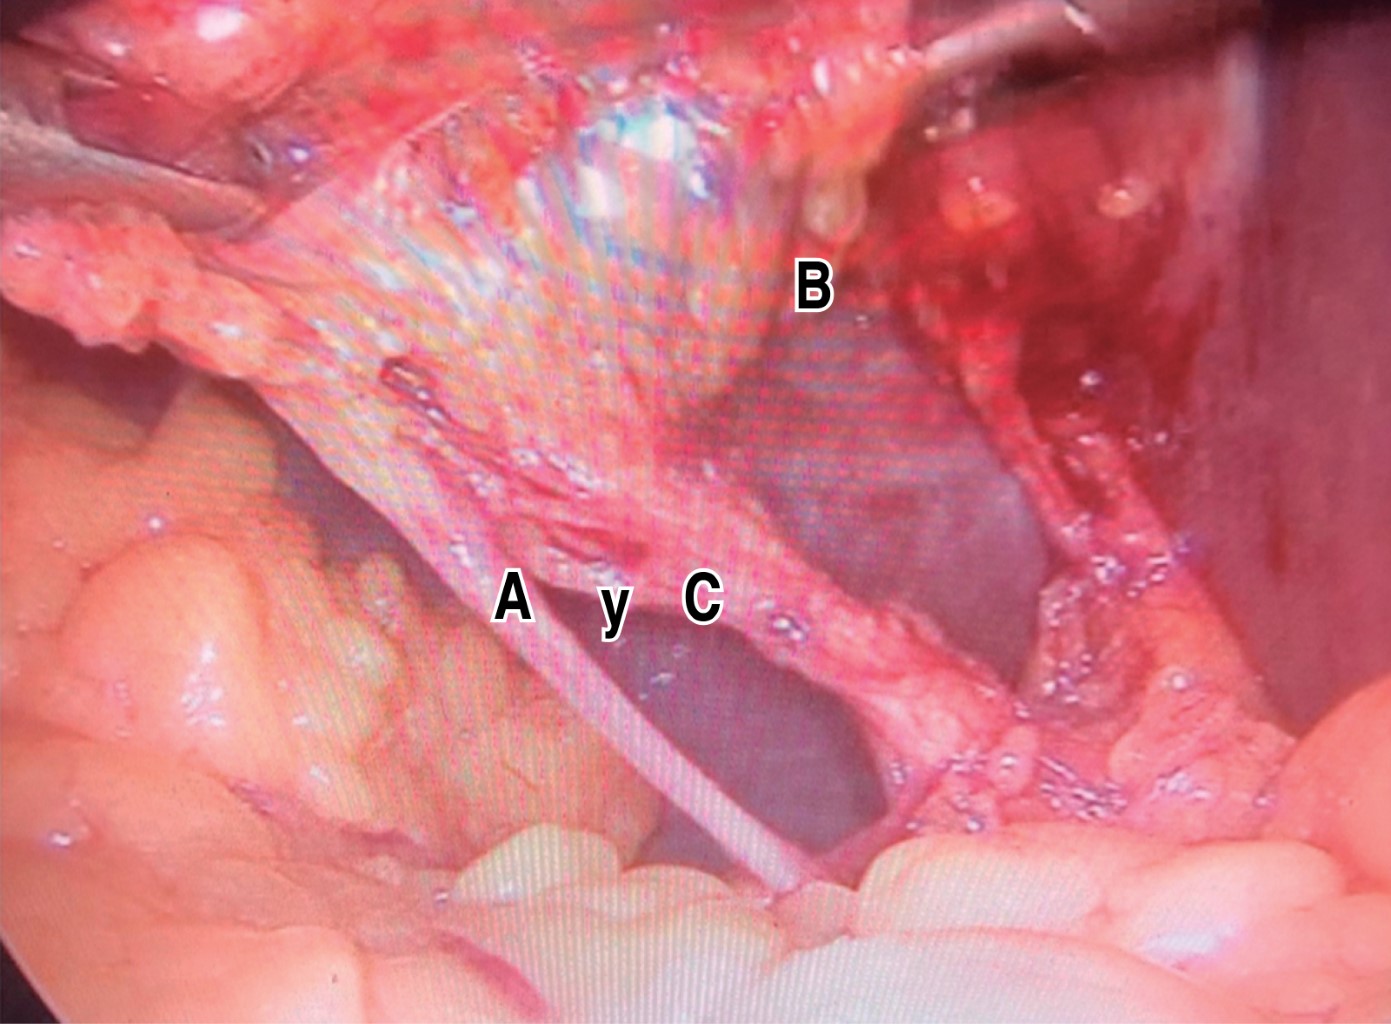

18. IN WHICH CASES IS IT RECOMMENDED TO PERFORM THE "CRITICAL SAFETY OVERVIEW"?

Always. Strasberg's critical view of safety has three dissection goals, which are maintained as the first recommendation for the culture of safe cholecystectomy. These goals consist of 1) complete dissection (anterior and posterior) of the hepatocystic triangle freeing fatty and fibrous tissue to observe and identify, in a complete manner, the cystic artery and cystic duct, 2) exposure of the lower third of the gallbladder bed, and 3) observe two and only two tubular structures entering the gallbladder corresponding to the cystic artery and cystic duct.66

By obtaining this safety-critical view, within this dissection space, up to 95% of the vascular variations and more than 80% of the anatomical variants of the extrahepatic bile duct can be identified.

If this critical safety view is not possible, it is recommended a salvage procedure, such as subtotal cholecystectomy and drainage, derivative cholecystostomy, or conversion to open surgery be considered 1,56,66,69,70,74-80 (Figure 1).

Percentage of agreement: 100%. Level of evidence: 1, grade: A, grade of recommendation: strong.